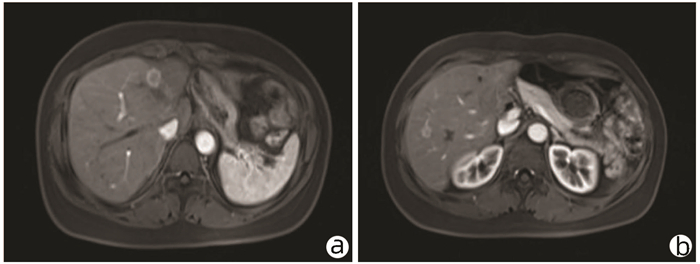

以亚急性肝衰竭为首发表现的IgG4相关性自身免疫性肝炎1例报告

蒋黎, 刘慧敏, 毛青

2022, 38(1): 170-173. DOI: 10.3969/j.issn.1001-5256.2022.01.028

摘要(1571) HTML (431) PDF (3941KB)(81)

摘要: